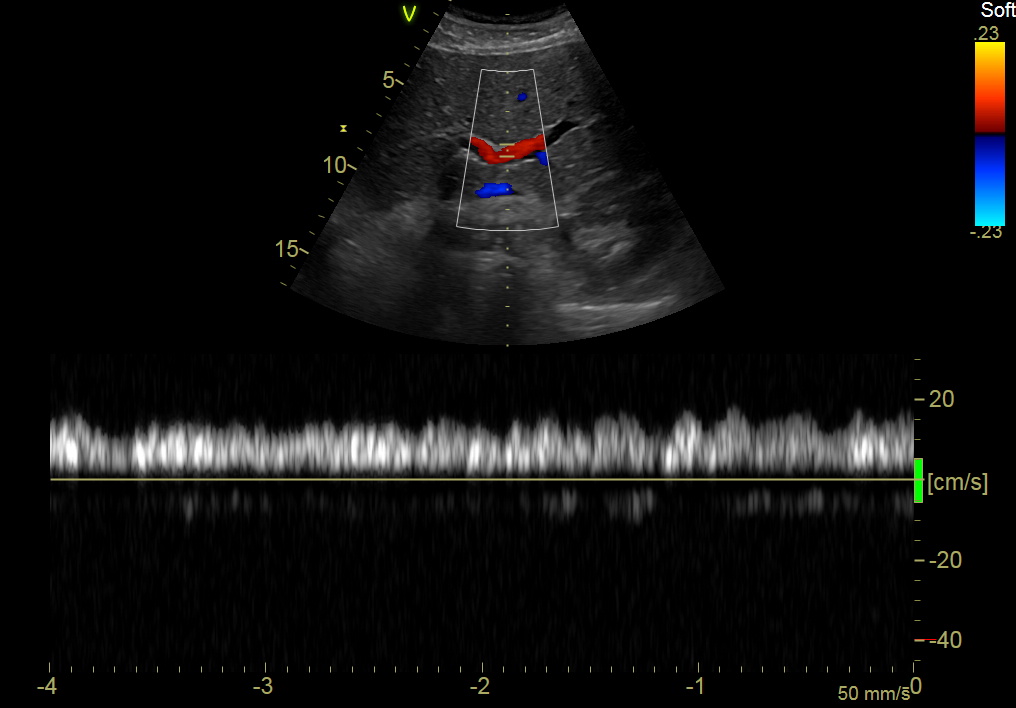

GE C1-6-D Abdominal Convex Refurbished

GE Convex C1-6-D Abdominal

Intended use

Abdominal and Women’s Health

Frequency Range

6 – 1 MHz

GE C1-6-D Abdominal Convex

Frequency Range: 6 – 1 MHz

GE C1-6-D Abdominal Convex for Abdominal and Women’s Health